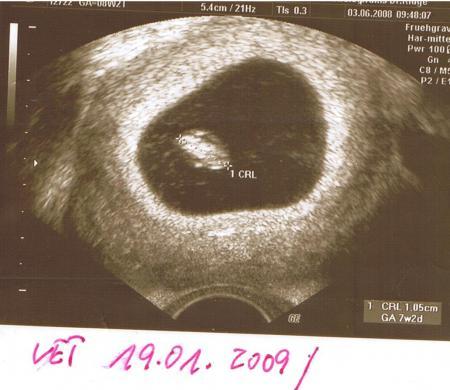

Hallo zusammen, ich bin heute 7+2. Letzten Dezember hatte ich eine MA in der 11.SSW mit Ausschabung und nach einem Zyklus Pause hat es gleich wieder geklappt. Ich war bei 5+0 bei der FÄ und da sagte sie schon "Hoppla, da sehen wir aber schon viel". Die Fruchthöhle war 7 mm groß, was mehr als doppelt so groß ist, wie normal bei 5+0 (3mm). Ich kann aber auf keinen Fall weiter gewesen sein, denn da ich Hormone nehme, wurde das genau überwacht wann der ES war. Donnerstag war ich dann bei 6+6 wieder da. Erstmal sahen wir einen absolut zeitgerecht entwickelten Embryo (9mm) mit kräftigem Herzschlag. Soweit erstmal gut :-) Auch Dottersack und Nabelschnur sahen gut aus. Aber die Fruchthöhle war 30mm groß, was 8+1 entspricht, normal wären 20mm gewesen... Die FÄ meinte gleich: "Oh Sie haben aber viel Fruchtwasser, ich suche mal einen Zwilling", aber da war kein Zwilling. Daher beunruhigt mich die Abweichung von 6+6 (Embryo) und 8+1 (Fruchthöhle) schon ziemlich. Wobei ich nochmal betonen muss, dass die Abweichung nicht durch eine Entwicklungsverzögerung des Embryos kommt, denn der ist genau wie er bei 6+6 sein muss und weiter kann ich noch nicht sein. Er hat also quasi einfach zu viel Platz. Google sagt mir, dass das ein erhöhtes Abortrisiko bedeutet. Auch dass es auf einen genetischem Defekt hindeuten kann. Hatte jemand von euch zufällig am Anfang der SS auch eine zu größe Fruchthöhle? Wie ist es bei euch ausgegangen? Ich habe natürlich große Angst, dieses Kind wieder zu verlieren... :-( Danke für eure Antworten!

ja ich hatte auch ne riesen Fruchtblase... sah das selber... aber der Arzt meinte es wäre alles normal... naja im Endeffekt ging die Geburt nicht voran weil die Kleine durch das viele Fruchtwasser nicht an den Muttermund ran kam... zum Schluss wurde dann die Fruchtblase aufgemacht und es ging dann richtig schnell... sonst hatte ich keine Probleme... außer nen Riesenbauch... Kind ist auch gesund... das war meine bei 7+2

Bild zu